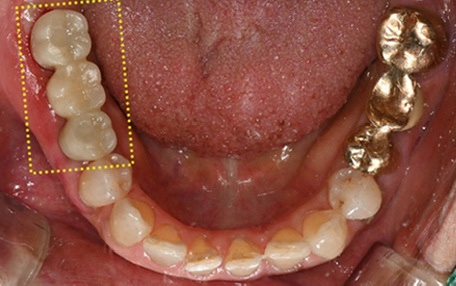

A treatment that applies to more people than expected

A sinus lift is not a treatment performed only in very special cases.

Among people planning upper molar implants,

there are quite a few cases where, during the examination process,

they are told that a sinus lift is needed.

In particular,

if it has been a long time since the tooth was extracted,

if the gum area in the upper molar region has significantly receded,

or if dentures have been used for a long time,

this is a treatment that is naturally considered.